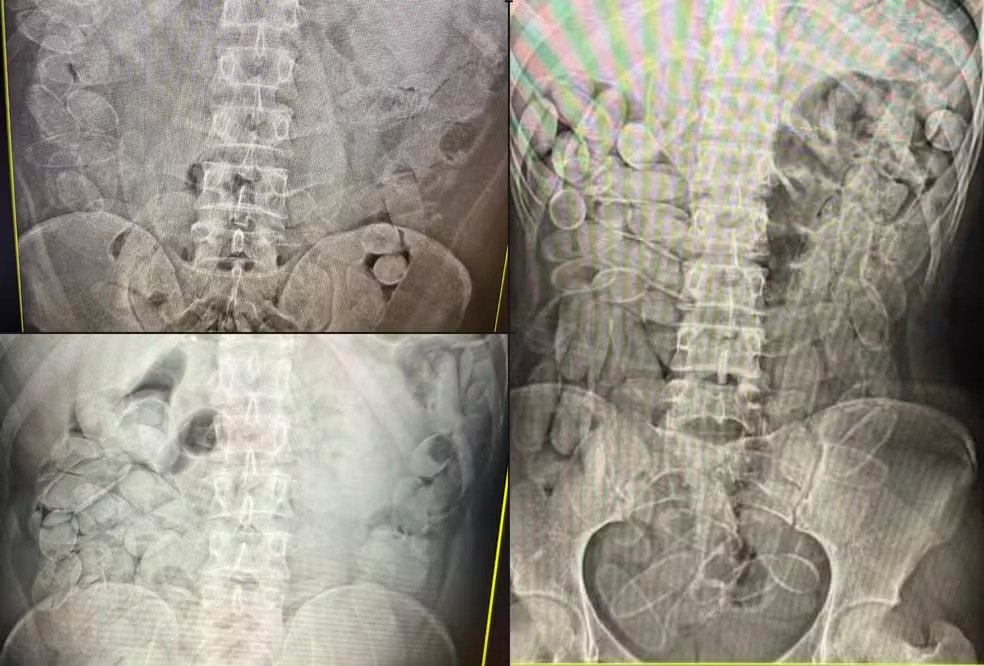

Quatro imagens de raio-X do abdômen mostrando múltiplas moedas dentro do trato gastrointestinal.

Cada pessoa engole, em média, cerca de 100 cápsulas de cocaína em tráfico internacional — Foto: Receita Federal

Quando há suspeita de transporte interno da droga, a pessoa é levada a uma unidade de saúde para exames de imagem. Se a presença das cápsulas for confirmada, o paciente passa a ser acompanhado por médicos até a eliminação ou retirada do material.

O método mais utilizado é a ingestão de cápsulas de cocaína. Cada pessoa ingere, em média, cerca de 100 cápsulas, o que totaliza aproximadamente 1,1 quilo de pasta base de cocaína por pessoa, conforme a auditora-fiscal da Receita Federal Tatiane Laranjo Amadeu Suhogusoff

“A droga fica dentro do corpo e não aparece em scanners de bagagem comuns. Para identificar, é necessário uso de cães farejadores e exames de raio-X, o que exige estrutura e efetivo que nem sempre estão disponíveis”, explicou a Helberth, representante da ANTT.